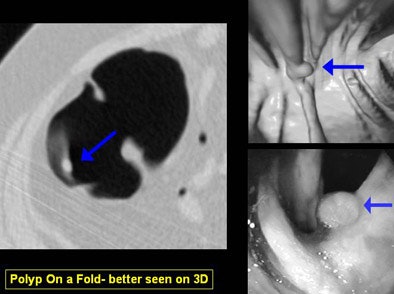

"You can differentiate folds from polyp and easily detect polyps on folds," she said. "And as shown in the Pickhardt study, you can achieve really high levels of sensitivity and specificity."

The primary 3D reader can also deviate from the flight path at any time to evaluate suspected lesions, and software can track which areas of the mucosa have been examined, Yee said. 3D can demonstrate complex, bulbous, or merging folds better than 2D.